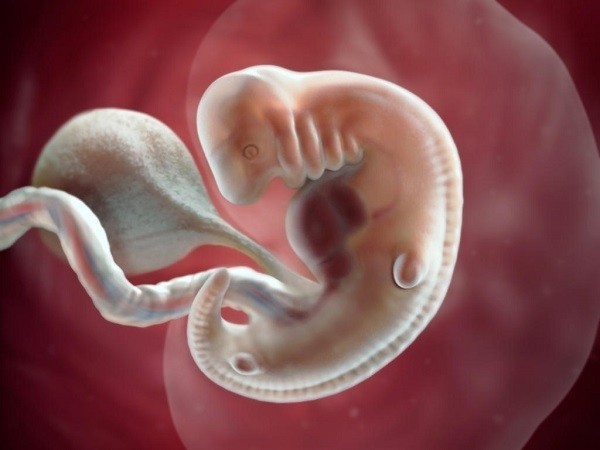

Từ tuần 7 thì con đã chớm hình thành các đầu ngón tay, ngón chân có màng, phần đuôi mở rộng của xương cụt cũng dần biến mất. Hệ thần kinh đã bắt đầu phân nhánh, tạo thành hệ sơ khai. Con đã dần xuất hiện mí mắt và cả ống thở kéo dài từ cổ họng đến nội tạng phổi.

Thai nhi 7 tuần phát triển bình thường có các đặc điểm như sau:

– Bàn tay, bàn chân dần dần xuất hiện các ngón kèm màng bảo vệ

– Phần xương đuôi bắt đầu co lại, và có thể đã biến mất.

– Các cơ quan nội tạng bé đang phát triển vượt trội, ống thở đã dần xuất hiện và vận chuyển oxy từ cổ họng đến các nhánh phổi

– Bé đã có mí mắt, và nhiều bé màu mắt cũng dần được lộ ra ngoài.

– Tai đã dần hình thành, lưỡi và các chân răng cũng đã có.

– Bộ phận sinh dục chưa phát triển toàn diện, khó có thể biết được là trai hay gái.